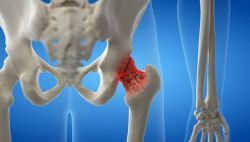

- Điều trị ngoại khoa các trường hợp gãy xương do loãng xương: Gãy cổ xương đùi: Thay chỏm xương đùi, thay khớp háng toàn bộ. Gãy lún đốt sống: Phục hồi chiều cao đốt sống.